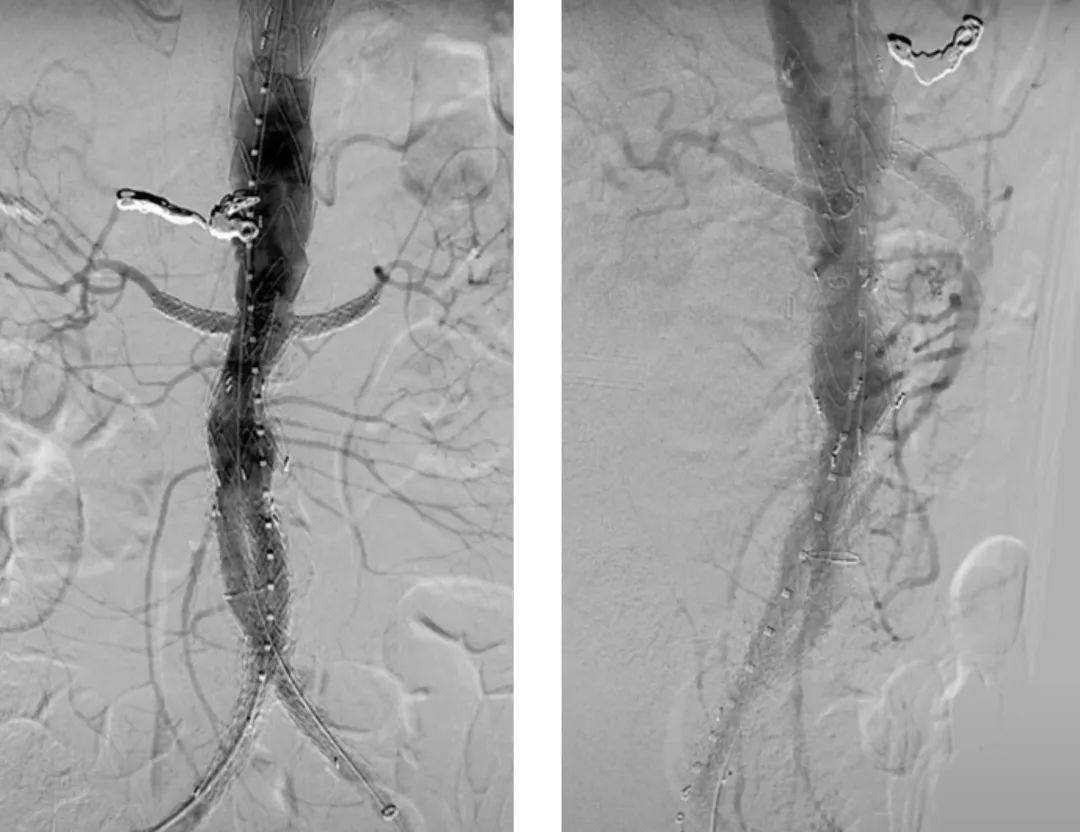

最后进行内脏动脉部分主动脉造影。注意在肾下有足够的空间(约5cm)以植入后续支架。使用普通EVAR支架完成后续的工作。

最后的正/侧位造影显示瘤腔隔绝满意,支架形态良好,主髂动脉及内脏分支动脉血流通畅。术中内脏动脉的总缺血时间<60min,肠系膜上动脉通畅在10-15min以内。

术后即刻造影